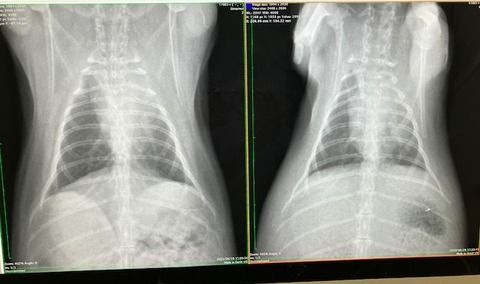

胸の方は

こちらも大きな問題なさそう、ですが、

心臓の輪郭がはっきりしてない箇所があります。

(向かって右上、白くモヤってるところ)

こちらは、ちょうど3年前、

去勢手術の術前検査で撮影したレントゲンがあったので比較すると、

ほとんど変化がありません。

肺の一部が弱ってる(しぼんでる?)のかなと。

(うさぎは肺が6個やったっけか?

1つ2つ機能しなくなっても生活に支障はない、とか…

過去の記憶ですが💦)

また、生まれつき(先天性)かも。

※緊急性の高い呼吸困難の症状が出ていない場合での見解です※

(向かって左が現在)

なので、リンパ腫などの可能性は低く、肺の一部が弱ってる(しぼんでる?)のかなと。